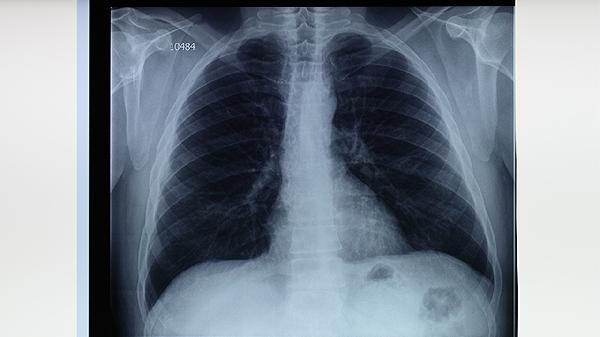

肺結(jié)核患者宜食高蛋白食物如雞蛋羹、鯽魚湯,忌辛辣燥熱之物。太極拳八段錦調(diào)節(jié)呼吸功能,每日晨起拍打肺經(jīng)穴位。居住環(huán)境保持通風(fēng)干燥,餐具煮沸消毒,痰液需用石灰處理。治療周期至少6個(gè)月,中途不可擅自停藥,定期復(fù)查胸片觀察病灶吸收情況。夜間盜汗明顯者可用浮小麥30克、糯稻根20克煎湯代茶飲。